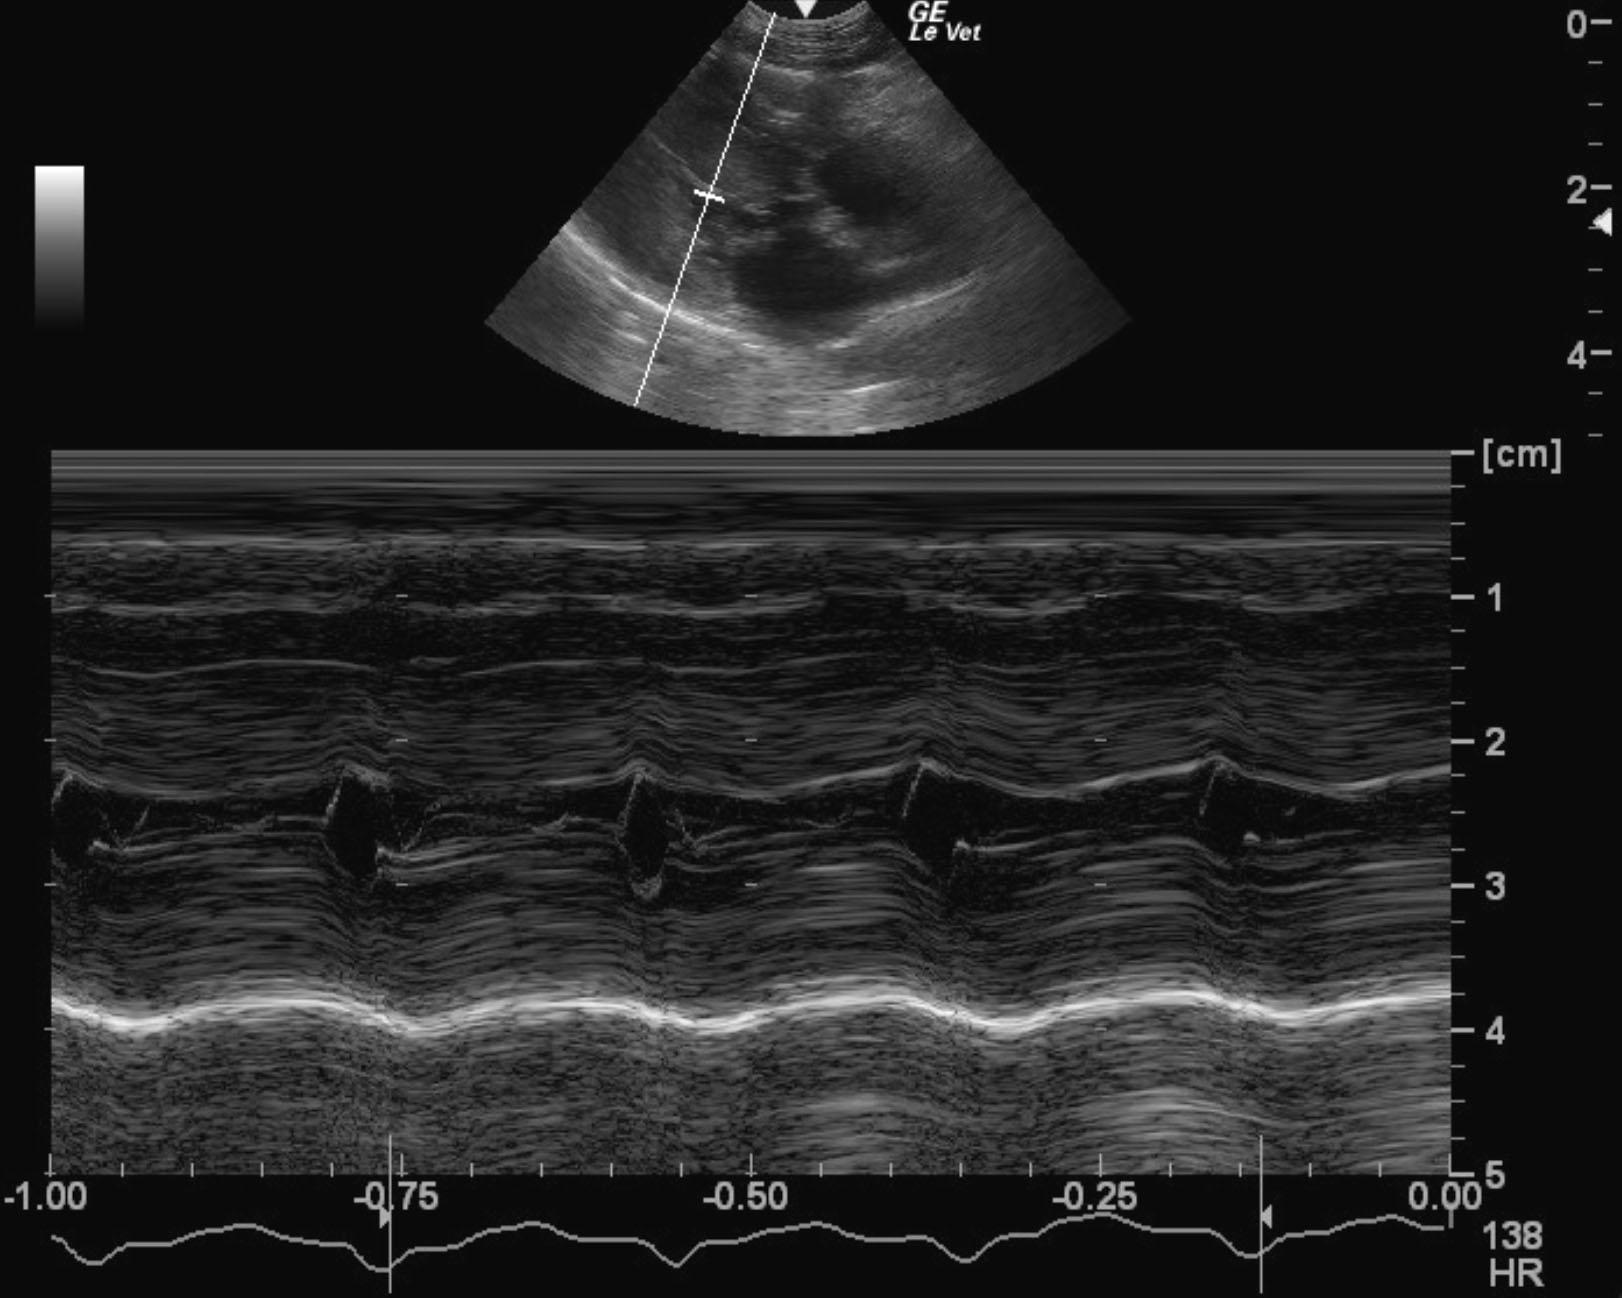

A 1-year-old MN DSHcat with a history of cardiac disease that was being treated with Plavix, enalapril, pimobendan, furosemide, and atenolol was presented for evaluation of weakness and dyspnea.

Physical exam: tachycardia (200-400bpm) and a grade III/VI heart murmur